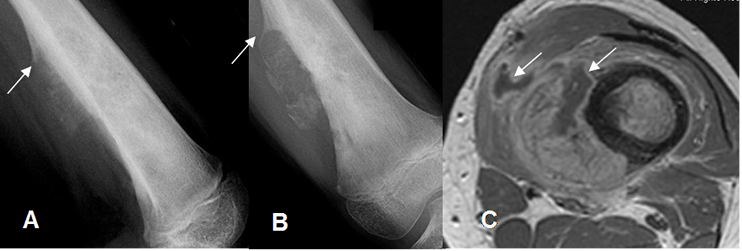

Fig 71 C. Osteosarcoma.

A: Rx lateral y B: Rx AP. Lesión permeativa en el fémur distal, con reacción perióstica en triángulo de Codman y masa de tejidos blandos.

C: RM axial en T1 con contraste. Masa de tejidos blandos que realza con el contraste, con áreas de necrosis.